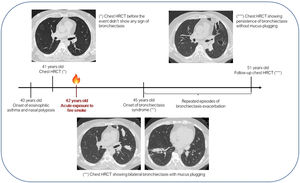

Inhalation injury remains one of the most challenging injuries for burn care providers. Long-term complications of smoke inhalation have rarely been reported in literature and these may be an unusual cause of bronchiectasis.1 In this letter to editor, we discuss the occurrence of radiological and clinical evidence of bronchiectasis syndrome three years after acute exposure to fire smoke in a Caucasian non-smoker asthmatic patient. At the age of 40, he was diagnosed with mild persistent eosinophilic asthma and nasal polyposis and started ICS/LABA (inhaled steroids and long acting beta2-agonist receptor) therapy. Nasal polypectomy was performed three years after asthma onset without any histologic evidence of vasculitis. Family history for pulmonary disease was unremarkable. At the age of 41, in the follow-up of previous papillary thyroid cancer, he underwent a chest high-resolution computed tomography (HRCT), which excluded any pulmonary or bronchial abnormalities. One year later he aided during a house fire where he was exposed to fire burn over 15-minute and he inhaled large amounts of smoke without wearing adequate protective equipment. At the end of the intervention, he did not complain of physical injuries, therefore he didn't seek referral to any physician. Three years later he presented to pneumological visit for worsening of respiratory symptoms, complaining about productive cough, worsening of dyspnoea, wheezing and chest tightness. Chest auscultation revealed inspiratory and expiratory wheezes. Lung function tests showed a mild restrictive ventilatory defect and a mild reduction of DLCO (Diffusion Lung CO), that were not present in previous tests. Chest x-ray showed bilateral opacities. On the hypothesis of asthma exacerbation with pneumonia, the patient was treated with oral corticosteroids and antibiotic therapy, with improvement of symptoms. For diagnostic purposes he repeated a chest HRCT that showed the presence of bilateral, large and saccular bronchiectasis with mucoid impact (Fig. 1). Moreover, it confirmed the presence of left basal pneumonia. To identify the bronchiectasis aetiology, several tests were performed. Blood analysis showed high eosinophil cell count (Eos 1.22 × 10^3/mmc), normal immunoglobulin levels (except for total IgE 218 UI/ml), negative autoimmunity screening (in particular Anti-nuclear antibody (ANA) and Antineutrophil Cytoplasmic Antibodies (ANCA)). No specific IgE for Aspergillus fumigatus were identified. Sweat test was also performed, with a negative result. Bronchoscopy with broncho-alveolar lavage (BAL) and transbronchial biopsies showed non-specific lymphocytic, histiocytic and eosinophilic inflammation, with negative microbiologic findings (including bacterial, mycobacterial and fungal culture, bacterial and virus PCR assays, and galactomannan on BAL). Several sputum cultures were also performed, always with negative results for bacteria, fungi and mycobacteria. In summary, the extensive diagnostic workup excluded immune deficiency, rheumatologic diseases (in particular eosinophilic granulomatosis with polyangiitis), cystic fibrosis, allergic bronchopulmonary aspergillosis, chronic bacterial or mycobacterial infections. In subsequent years the patient reported several episodes of bronchiectasis exacerbation for which he underwent several courses of antibiotic therapy. Radiological follow-up by chest HRCT confirmed the persistence of saccular bronchiectasis (Fig. 1), which remained stable overtime.

There are no standardised criteria for inhalation injury diagnosis, which is usually based on clinical history and findings, with the help of instrumental tests (i.e. HRCT, carboxyhaemoglobin measurement and fiberoptic bronchoscopy).2 Many of the airway consequences of smoke inhalation result from an inflammatory response and they depend on the duration and the magnitude of the exposure, the presence of particulate matter and individual host factors. Many products of combustion, such as halogen acids, formaldehyde, and unsaturated aldehydes act as respiratory irritants.3 Long-term complications have been poorly studied and include bronchiectasis, bronchiolitis obliterans, endobronchial polyposis, tracheal and main bronchial stenosis. These complications have been mainly described as chronic consequences of an acute pulmonary manifestation (i.e. endobronchial steam burns, pneumonia and acute respiratory distress syndrome ARDS).1 It is worth noting that our patient developed clinically significant BE three years after acute smoke exposure, apparently without acute pulmonary manifestations. Few cases like the one presented have been described in the literature. Putman et al.4 analysed radiographic manifestations in a cohort of 21 patients after acute smoke inhalation and noted that one patient subsequentially developed significant chronic lung disease with BE at a 10-months follow-up evaluation. Slutzker et al.5 described a patient with progressive dyspnea and chronic productive cough with multiple exacerbations for 11 years after acute smoke inhalation injury, who was finally diagnosed with saccular bronchiectasis.

In our patient, some important points should be addressed: first of all, the lack of a medical evaluation soon after the event; second, the possibility of an interrelationship between asthma and bronchiectasis, even in the absence of ABPA. Indeed, long-standing asthma per se might have complicated with bronchiectasis on chest imaging.6,7 However, our patient had normal chest HRCT at baseline. The presence of eosinophilic asthma may have caused predisposition to the development of bronchiectasis in which smoke and irritants inhalation may have acted as a trigger. Arguments in favour and against our hypothesis are summarized in Table 1.